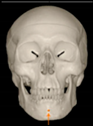

Three points determined the Acta plane: O, F right (FR), and F left (FL) (Table 2). Point O is the midpoint between the most craniodorsal point of the dorsum Sella and the most posterior dorsal point of the Basion in the midsagittal plane (Figure 1). Both points F are a result of the intersection between two lines: the line that connects the most inferior points of the lower orbital margins, right and left, and a line perpendicular to this line that runs through the most external points of the orbital margins, right and left (Figure 2). The new transverse reference plane, the Acta plane (Figure 2), is created by connecting the O-point (Figure 1) with FR and FL (Figure 2).

Figure 2.

(A) Construction of the F-points (right and left), frontal view. The F-points are originated from the intersection between the line connecting points A (the most inferior point of the lower orbit) and the perpendicular line to it that passes through points B (most external/lateral point of the Orbita). (B) Transverse view of the ACTA plane.